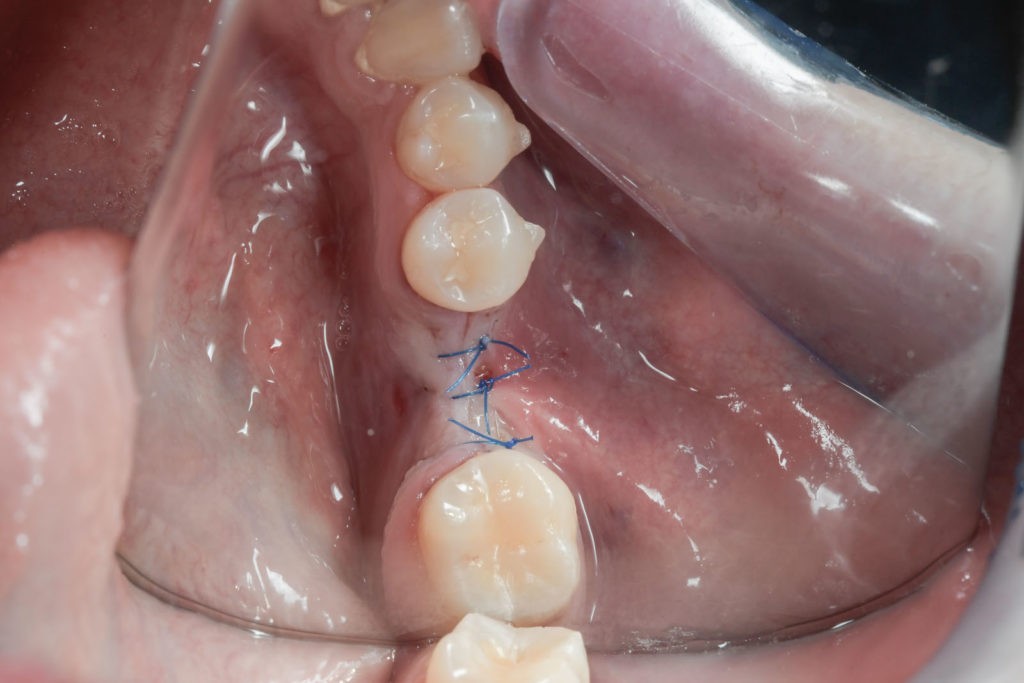

Zabieg odbudowy zębodołu powinno się wykonać możliwe jak najszybciej po usunięciu zęba. Jego celem jest odbudowa naturalnej objętości kości w miejscu utraconego zęba, a następnie szybkie wprowadzenie implantu. Najlepsze rezultaty uzyskuje się przy zastosowaniu biomateriału w formie bloczków kolagenowych lub granulatu, które dają trwałe efekty odbudowy oraz optymalną funkcję i estetykę odtworzonych koron zębów na wszczepionym implancie.

Regeneracja kostna polega na umieszczeniu w rekonstruowanej okolicy materiału kościotwórczego oraz pokrycie go specjalną błoną zaporową, dzięki której regenerowany obszar chroniony jest przed wrastaniem tkanek miękkich. Po kilku miesiącach na skutek działania procesów regeneracyjnych i remodelujących materiał ulega przebudowie na pełnowartościową, własną tkankę kostną pacjenta, w którą bez obaw można wprowadzić implanty stomatologiczne. Obecnie istnieje wiele innych protokołów regeneracyjnych dla kości, uwzględniających zastosowanie różnego typu błon zaporowych, siatek tytanowych oraz uzyskanych i odwirowanych z krwi autogennych czynników wzrostu.

Bloki kolagenowe używane są najczęściej do odbudowy geometrycznych, trójwymiarowych ubytków kostnych, których doskonałym przykładem jest zębodół po ekstrakcji zęba. Jest to jeden ze sposobów na procedurę „socket preservation”, czyli natychmiastową lub wczesną odbudowę zębodołów poekstrakcyjnych dla osiągnięcia optymalnych efektów estetycznej odbudowy protetycznej koron zębów na implantach.